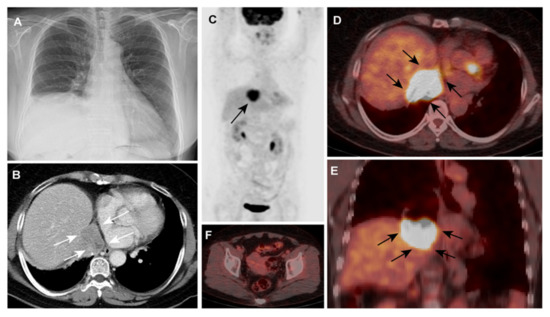

Incidental Detection of Ovarian Cancer as a Solitary Peridiaphragmatic Distant Lymph Node Metastasis without Pelvic Lesions on 18F-FDG PET/CT